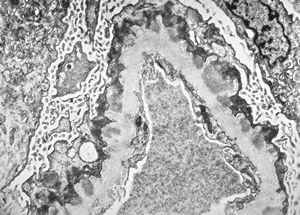

M,53y. | type III membranoproliferative glomerulonephritis